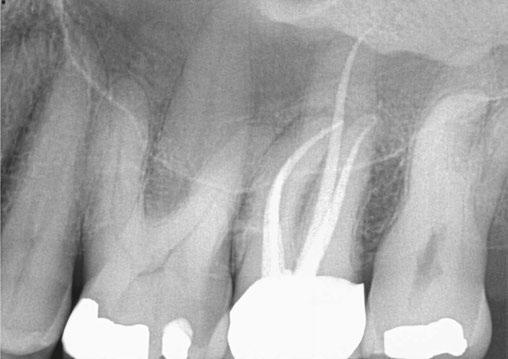

Figure 4 (left): Preoperative image of tooth No. 15. Figure 5 (right): Postoperative image. Rotary negotiation with Roto-reciprocation in all 3 canals with lengths from 25-28 mm and the ProTaper Ultimate Slider advanced to WL within 2 passes

After conducting research with the ProTaper Ultimate Slider and successfully negotiating to patency 80% of the time, I then experimented with a hybridized shaping system consisting of using the ProTaper Gold Shaper 1 (Dentspy Sirona) to prepare the middle 1/3 shape, and then following that with reciprocation using the WaveOne Gold Primary (Dentsply Sirona) to finish the apical shape. If a canal had a larger foramen than a No. 25 (tip size of the WaveOne Gold Primary), then I would “upshape” or “plus it” to a WaveOne Gold Medium (No. 35 tip).

In closing, the ProTaper Ultimate Slider has completely changed the way I negotiate to the apex. In over 1,300 cases I have been successful at reaching the apex and beyond 80% of the time. In the majority of these cases, I am able to negotiate to

patency, achieve an accurate working length, and an open glide path (three key endodontic pillars) in seconds. I then follow this up with a hybridized roto-reciprocation technique using the ProTaper Gold S1 to shape the middle third and then the WaveOne Gold Primary to shape the apical third. This roto-reciprocation technique also shapes the majority of canals in just minutes. I now have plenty of time to activate and enhance irrigation with different devices on the market or let the sodium hypochlorite or Triton (Brasseler USA) soak in the canals while I am diagnosing and anesthetizing another patient. All in all, I have been using this new hybridized roto-reciprocation technique for the last year and a half, and it has increased my shaping efficiency, simplified my technique, and has made root canal therapy enjoyable.